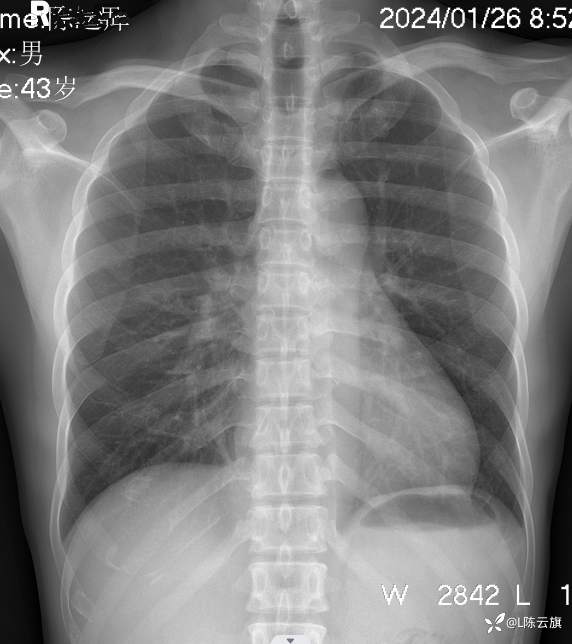

胸片3: